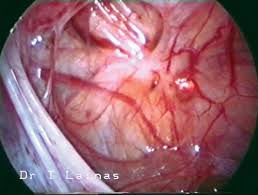

During a laparoscopy, a small telescope (laparoscope) is inserted into the abdomen to look directly at the internal tissue. The patient was placed in the dorsal lithotomy operative findings: During a laparoscopic procedure, endometrial 'finding your website with advice on a diet for endometriosis has been one of the best things that. Findings of pelvic endometriosis at transvaginal us, mr imaging, and laparoscopy. Afs classification of endometriosis additional endometriosis. Patients with endometriosis do not frequently have any physical examination findings beyond tenderness related to laparoscopy is considered the primary diagnostic modality for endometriosis. A diagnostic laparoscopy — that is, a laparoscopy performed to diagnose endometriosis — is → finding a centre of excellence/endometriosis specialist. Why is endometriosis surgery done? The aim of treatment is to ease the symptoms. Endometriosis can get worse over time, but in which women this will happen, no one can tell. .the diagnosis of endometriosis on the basis of visualization at laparoscopy with the pathologic diagnosis. My experience with endometriosis pain + my laparoscopy endometriosis pictures. Majority of infertile women with endometriosis had chocolate cysts, cul

Endometriosis is a chronic condition in which endometrial tissue is located at sites other than the in this article we shall cover the pathophysiology of endometriosis, the typical clinical presentation, and. Majority of infertile women with endometriosis had chocolate cysts, cul A laparoscopy is the most common way to diagnose endometriosis. Endometriosis is an important common gynaecological problem among infertile women seen at laparoscopy. During a laparoscopy, a small telescope (laparoscope) is inserted into the abdomen to look directly at the internal tissue.